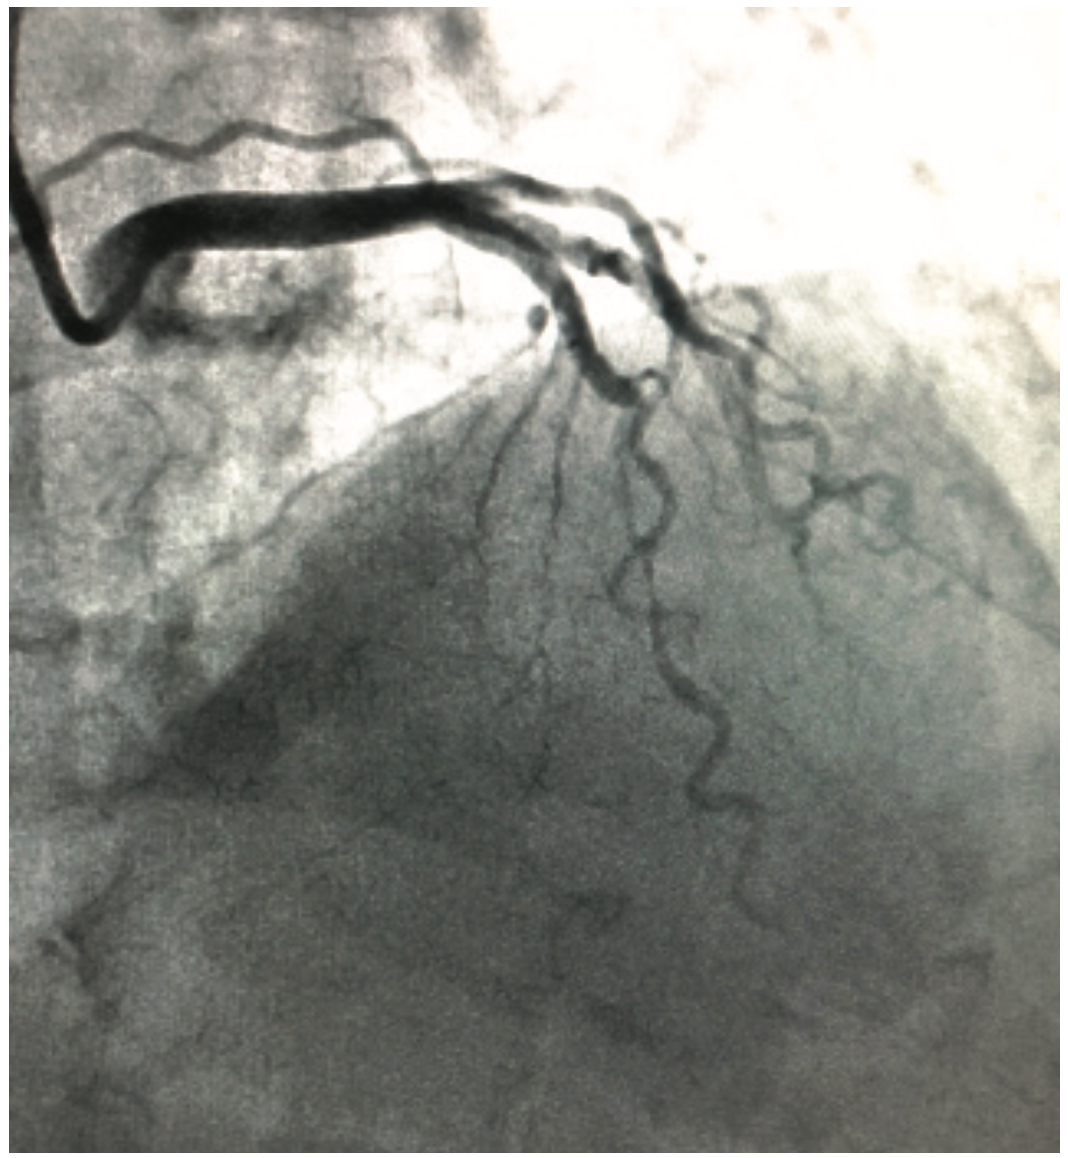

Although not common or rare, coronary bridging (myocardial bridge) is a congenital anomaly where a band of muscle lies on top of a coronary artery instead of below it. As a result, a portion of the vessel is revealed that dips into and underneath the heart muscle, and then back out again. The vessel is open during diastole (Figure 1) and compressed during systole (Figure 2).

Cardiac catheterization via a radial approach demonstrated minimal non-obstructive coronary artery disease, with a bridging effect in the mid LAD (Figures 1-2, Video 1). Optimizing medical management was the course of treatment.